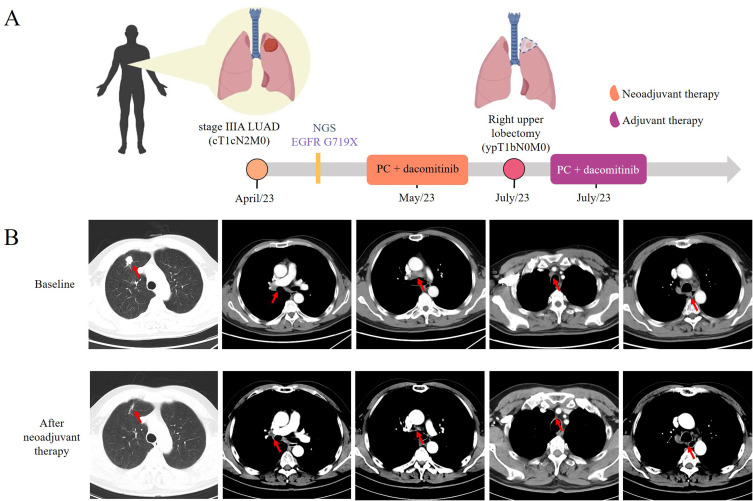

表皮生长因子受体酪氨酸激酶抑制剂(EGFR TKIs)的有效性已经得到证实,因此NCCN指南推荐将其作为晚期EGFR突变阳性非小细胞肺癌(NSCLC)患者的一线治疗。然而,对于EGFR突变阳性的III期NSCLC患者是否使用新辅助TKI治疗仍存在争议。在这里,我们首次报道了一名IIIA期肺腺癌患者,基于EGFR G719X突变,化疗和dacomitinib作为新辅助靶向治疗受益,实现了病理分期降低和根治性手术切除的机会。本病例描述了dacomitinib作为EGFR阳性晚期NSCLC的新辅助靶向治疗,并强调了分子检测在更好的治疗决策中的应用。

The effectiveness of epidermal growth factor receptor tyrosine kinase inhibitors (EGFR TKIs) has been established, leading the NCCN Guidelines to recommend it as a first-line treatment for patients with advanced EGFR mutation-positive non-small cell lung cancer (NSCLC). However, there is still controversy about the use of neoadjuvant TKI treatment for patients with stage III EGFR mutation-positive NSCLC. Here, we firstly report that a stage IIIA lung adenocarcinoma patient benefited from chemotherapy and dacomitinib as neoadjuvant targeted therapy based on EGFR G719X mutation, achieving a pathological downstaging and the chance of radical surgical resection. Our case describes dacomitinib use as neoadjuvant targeted therapy for EGFR positive advanced NSCLC and highlights the application of molecular testing for the better treatment decision making.